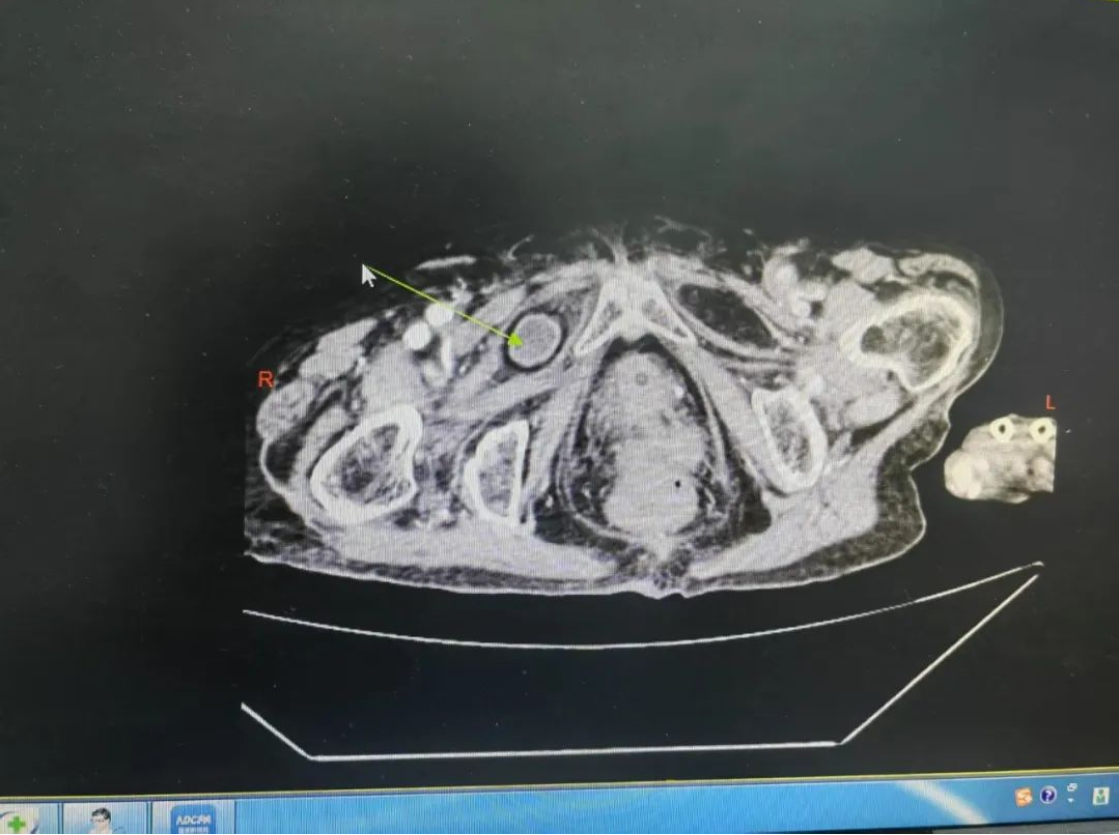

患者因剧烈腹痛腹胀急诊入院时,影像检查显示右侧闭孔嵌顿性疝引发急性肠梗阻,嵌顿肠管已呈现绞窄性坏死征象。面对高血压3级、冠脉多支病变、慢性阻塞性肺疾病等多重高危因素,医疗团队启动MDT应急机制:麻醉科定制闭环式靶控输注方案,运用血流动力学监测技术实现循环精准调控;影像团队通过薄层CT三维建模锁定直径0.8cm疝环解剖位置;重症医学科构建围术期呼吸支持及容量管理模型。经老年综合评估系统(CGA)量化风险指数后,手术团队果断决策实施限期手术。